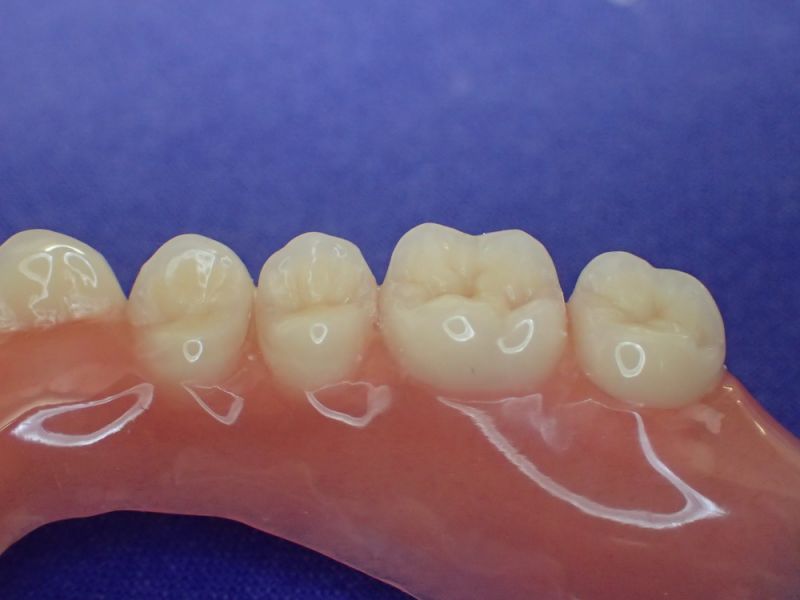

Nach inzwischen 12 jähriger Tragedauer wurden alle Kunststoffteile erneuert, das metallische Grundgeroüst der Arbeit erhalten und die Arbeit befindet sich in einem Zustand, der sich weitgehend an der Ersterstellung orientiert.

Bei derartigen Arbeiten ist es tatsächlich möglich grundlegende Konstruktionsmerkmale einer alten Arbeit zu übernehmen und Verschleißteile aus Kunststoff zu erneuern.

Im Prinzip ist das beliebig oft möglich und für den Patienten mit einer enormen Kostenersparnis verbunden.